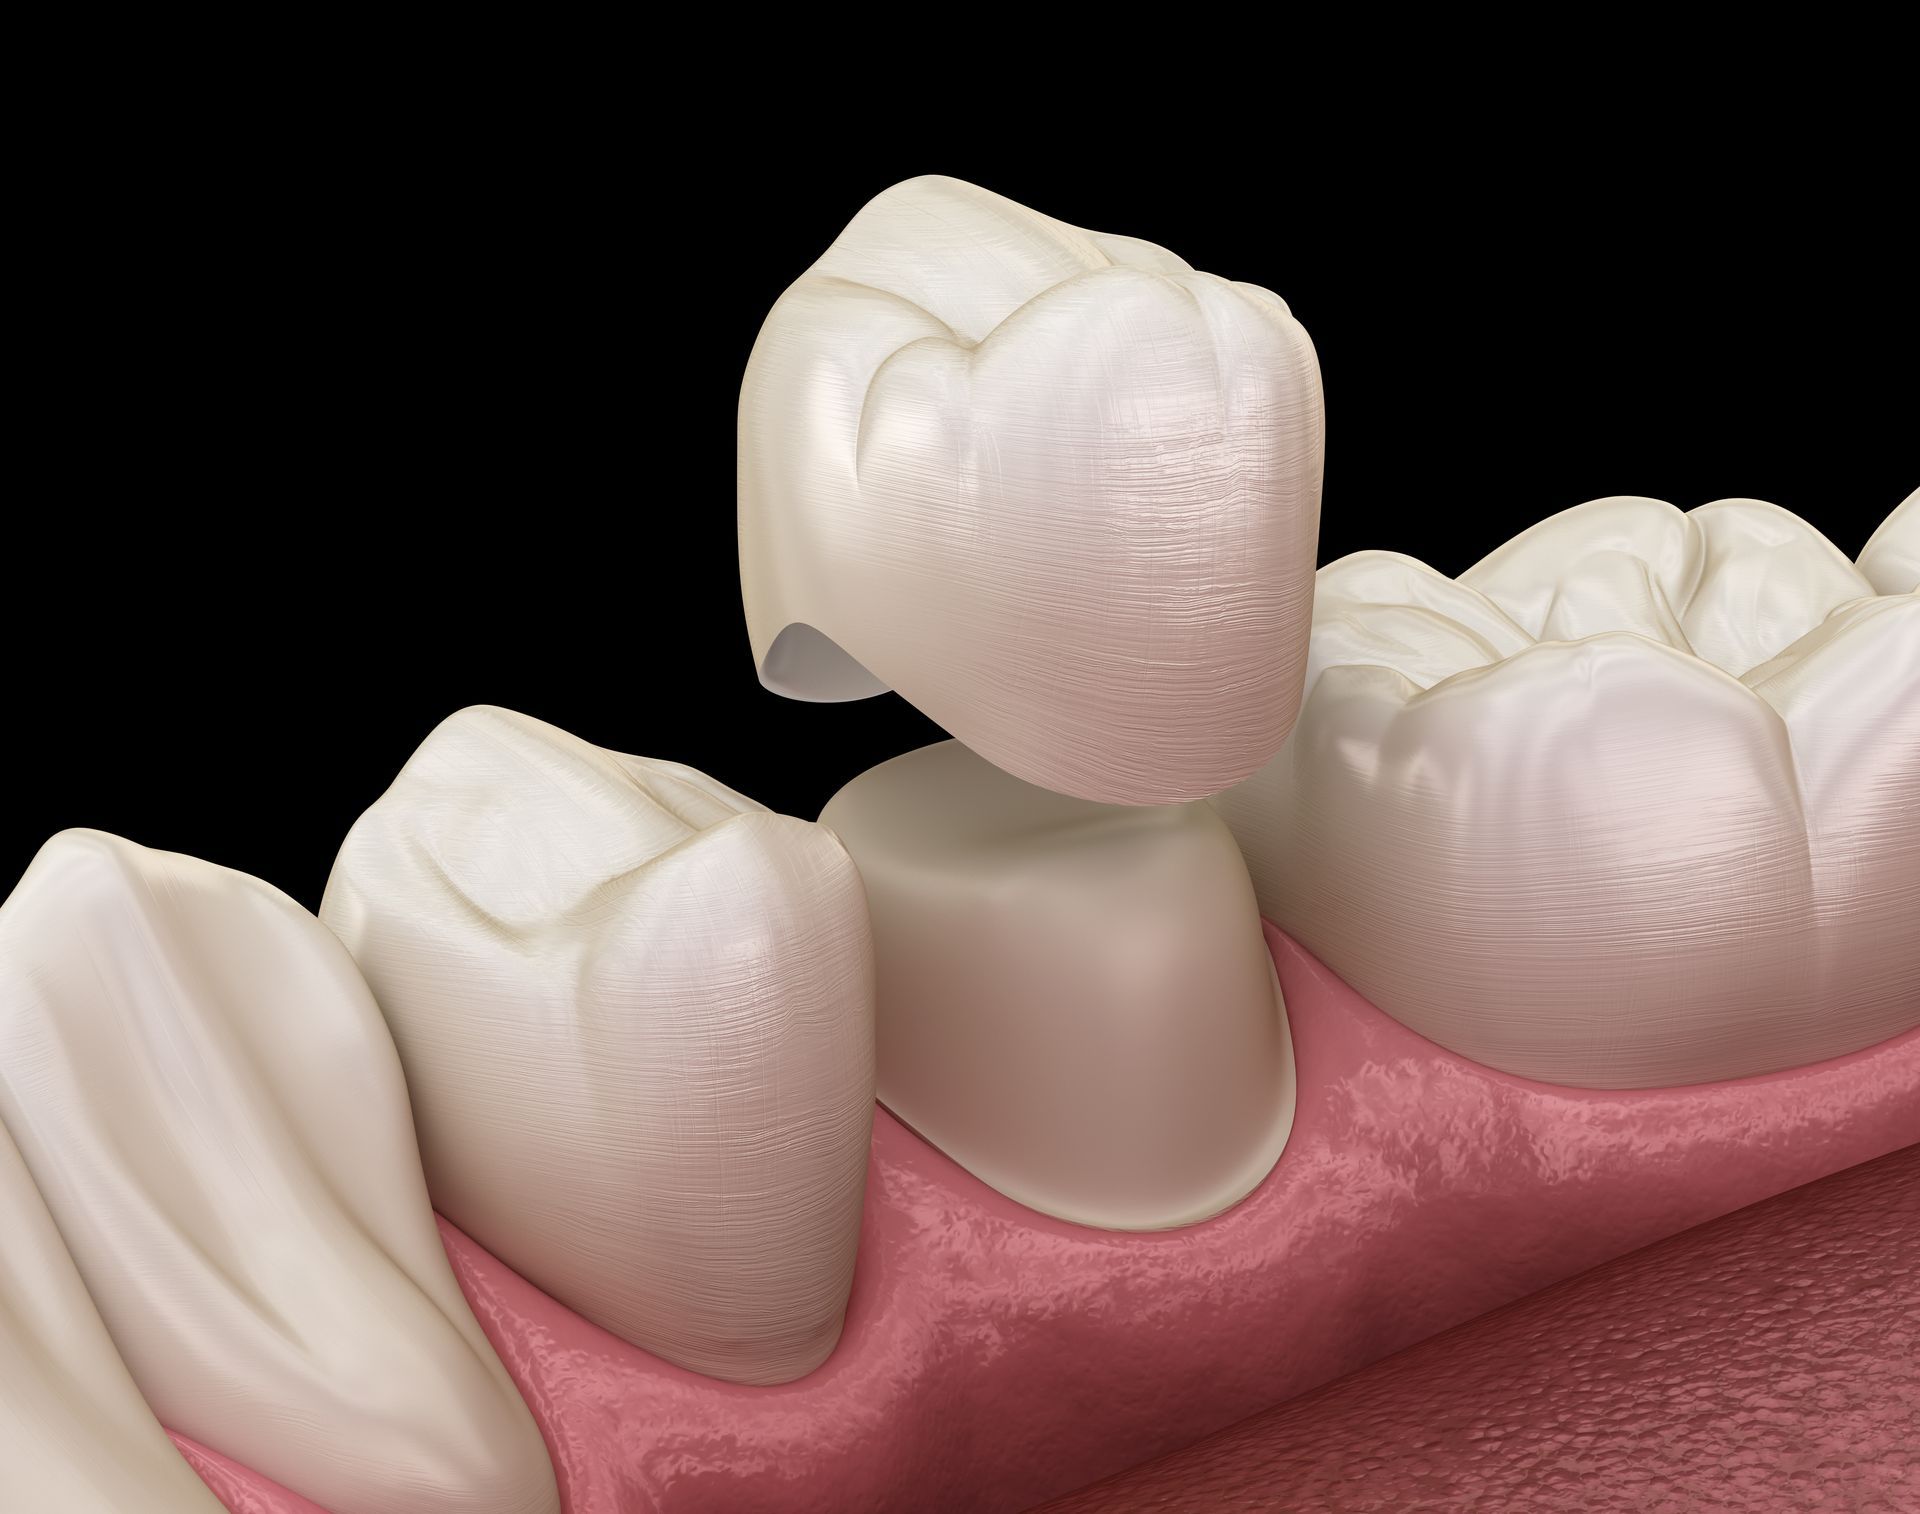

Implantologie

Nous offrons le service de restaurations sur

implant, la couronne ou le pont sur implant étant la solution de choix pour remplacer une dent manquante.